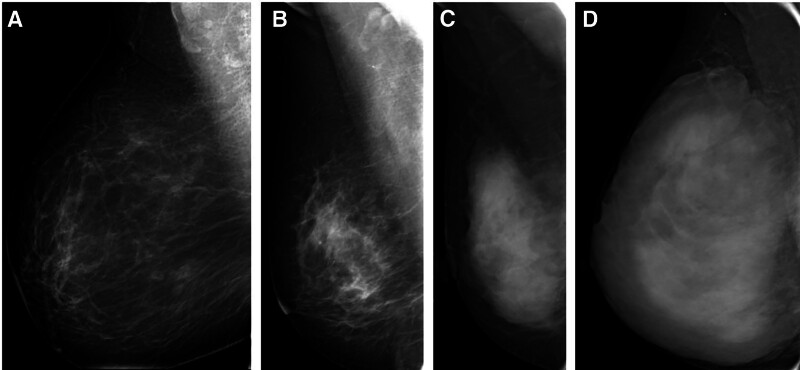

我们试图揭示乳腺癌(BC)风险与全场数字乳房x线摄影(FFDM)的乳房x线摄影密度(MD)和动态增强磁共振成像(MRI)的背景实质增强(BPE)之间的相关性。对2019年1月至2020年12月接受MRI和FFDM检查的216例女性进行了回顾性分析,其中72例BC经组织病理学鉴定。对照与BC病例按2:1匹配。FFDM患者的MD分为ACR a、ACR b、ACR c或ACR d。MR患者的BPE分为轻度、轻度、中度和显著4个级别。采用Logistic回归分析调查BC风险与BPE和MD之间的关系,得出比值比(or)。该研究对216名女性进行了回顾性研究,其中包括72例BC病例和144例正常对照。在BC病例中,64例患者被分级为ACR c或ACR d(88.9%), 40例患者被分级为中度或重度BPE(55.6%)。ACR c或d病例与ACR a或b的or分别为4.7和5.8 (P = 0.002)。与轻度或轻度BPE相比,表现出明显或中度BPE的or分别为5.0和3.3

We attempt to reveal the correlations between breast cancer (BC) risk with mammographic density (MD) in full-field digital mammography (FFDM) and background parenchymal enhancement (BPE) in dynamic enhanced magnetic resonance imaging (MRI). 216 women who received MRI and FFDM from January 2019 to December 2020 were reviewed, among which 72 BC cases were identified histopathologically. The control was matched with the BC case in 2:1. MD in FFDM were categorized as ACR a, ACR b, ACR c, or ACR d. BPE in MR was categorized into 4 grades, minimal, mild, moderate, or marked. Logistic regression analysis was utilized to investigate the associations between BC risk with BPE and MD, resulting in the odds ratios (ORs). The review was performed with a cohort of 216 women, including 72 BC cases and 144 normal controls. Among BC cases, 64 patients were graded as ACR c or ACR d (88.9%), and 40 patients were graded as moderate or marked BPE (55.6%). The ORs for ACR c or d cases versus ACR a or b were 4.7 and 5.8 for different readers, respectively (P = .002). The ORs for cases exhibiting marked or moderate BPE compared to mild or minimal BPE were 5.0 and 3.3 (P < .001). MD and BPE categories were identified as potential risk factors for BC. Increased levels of BPE or MD are strongly predictive of BC.